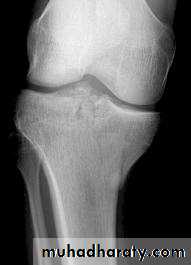

Tibial plateau fractures:

Direct blow or fall from height may cause fracture of one tibial condyle or both.

Fracture lateral condyle is the commonest named as bumper fracture

caused by a force that abducts the tibia upon femur while the foot is fixed on ground.

Patient usually is an adult, the knee joint is swollen, bruises, there is diffuse tenderness and doughy feel of haemarthrosis.

ligaments injuries must be excluded.

Imaging : X-ray

: anteroposterior, lateral & oblique views.

CT -Scan may used to detect amount of depression and comminuation.

Tibial plateau fracture